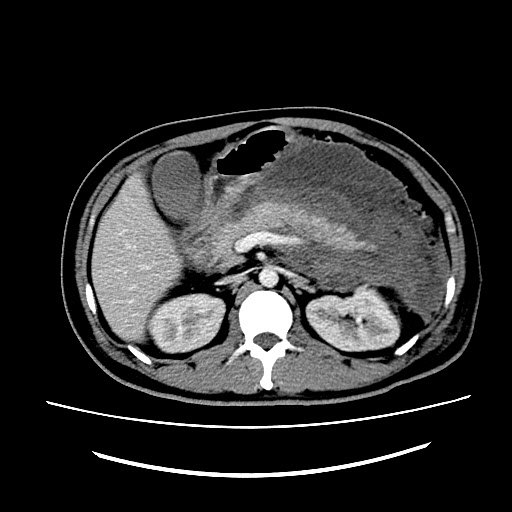

按照balthazar分级标准,急性胰腺炎在ct上可分为五级.

图4-3 急性胰腺炎a.ct平扫;b.ct增强动脉期;c,d.

术前ct提示重症急性胰腺炎合并胰腺周围感染和积脓经过经皮穿刺置管

通过ct检查,可以明确急性胰腺炎的分